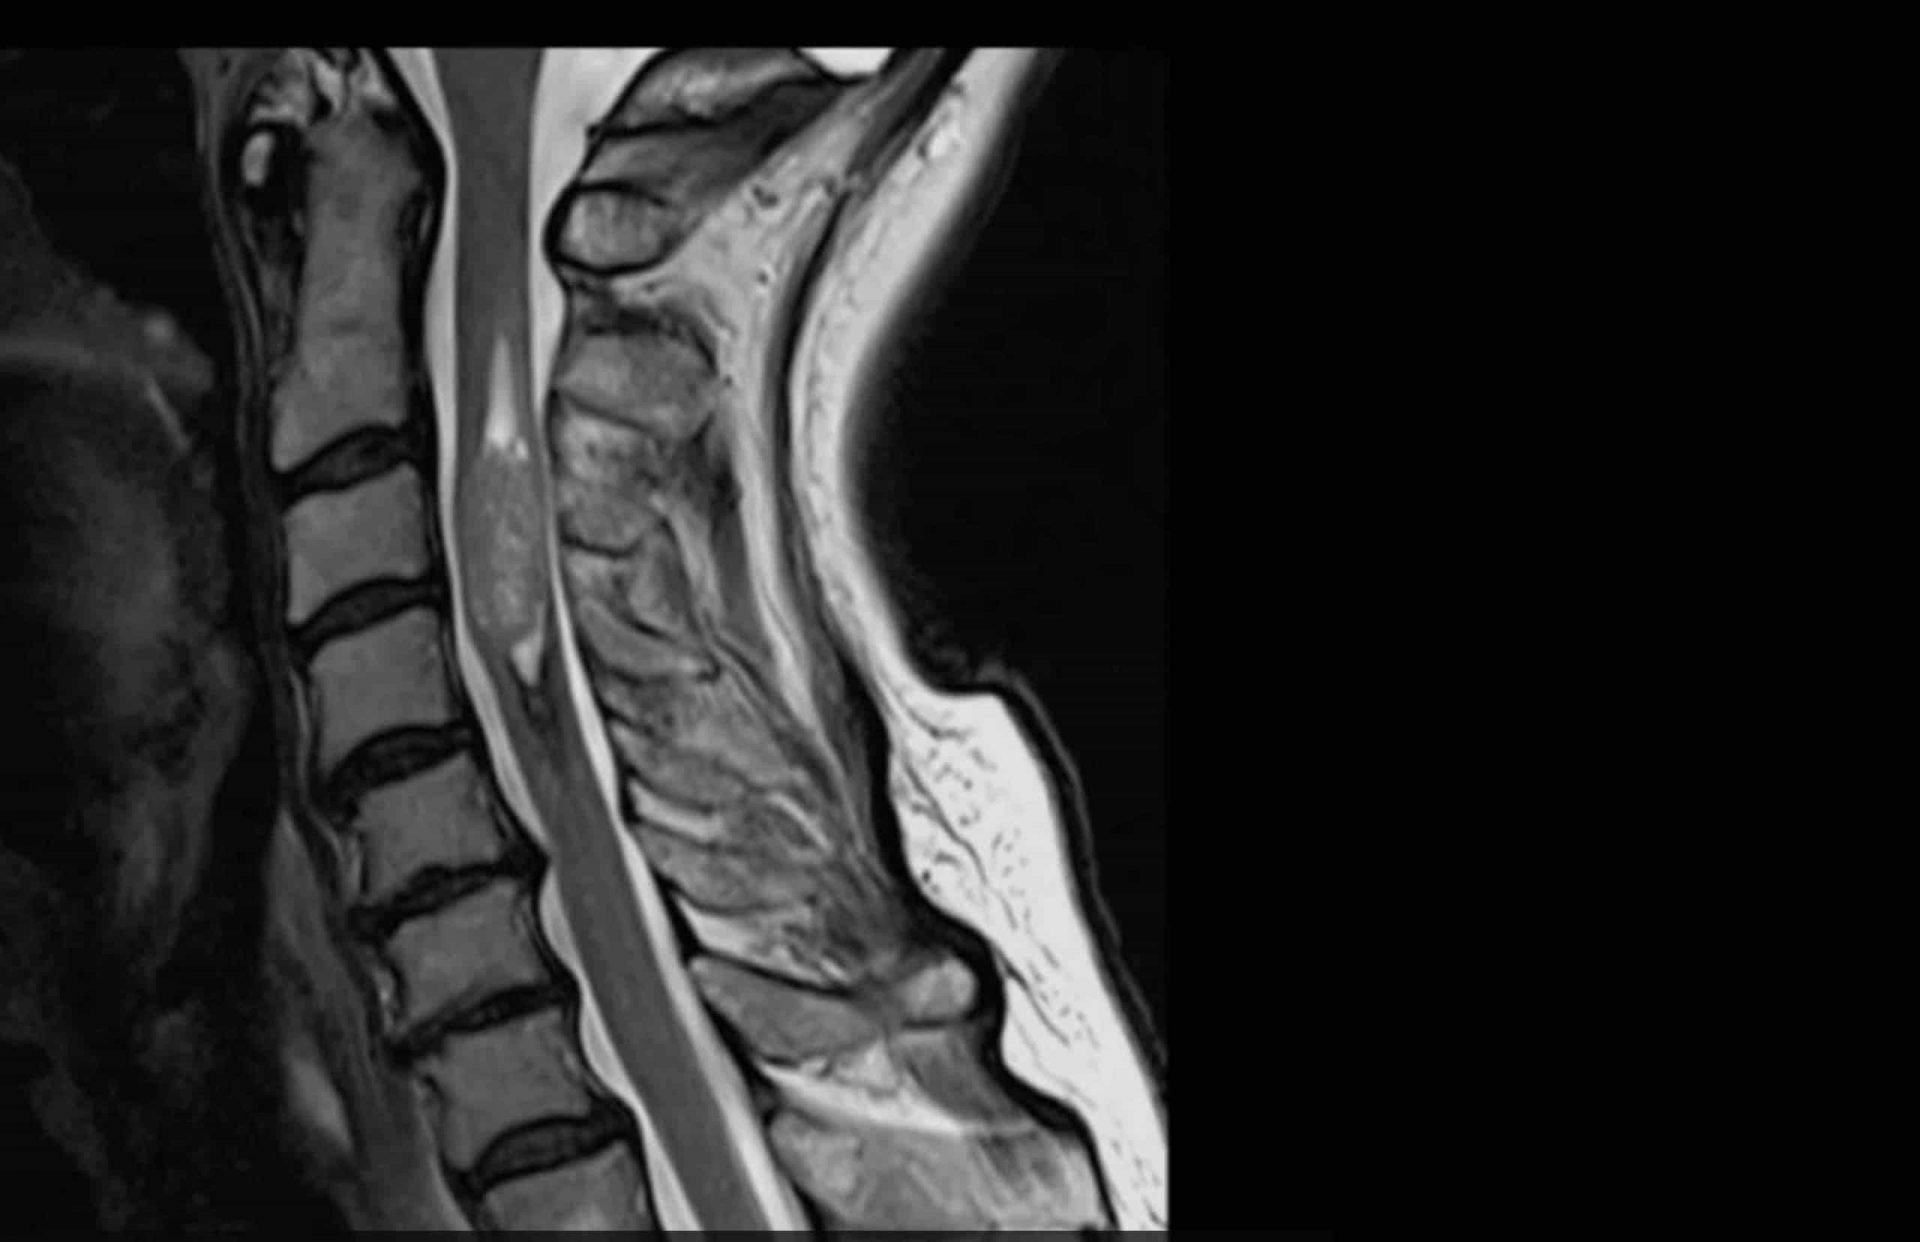

גידול בעמוד שדרה

הגידולים השכיחים ביותר הם אסטרוציטומה (astrocytoma) ואפנדימומה (ependymoma). גידולים אלה הם בתוך החומר של חוט השדרה. סרטן אחר כמו סרקומה מתפתח מהעצמות עצמן. מכאן שסרטן יכול להופיע מאחורי חוליות עמוד השדרה, בתוך עצבי חוט השדרה או במעטפת חוט השדרה. מבין הגידולים האלימים: כורדומה, וסרקומת יואינג.